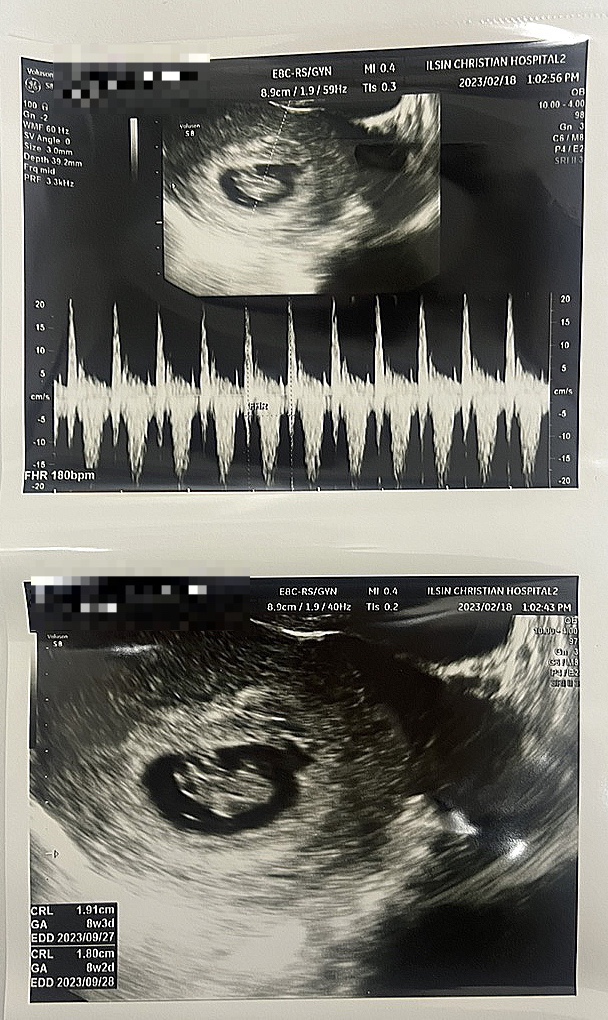

[임신 8주차]드디어 이등신이 된 또복이ㅋㅋㅋ(feat.기형아검사고민?)

병원다녀온지 한참 지났는데 이제서야 쓰는 또복이 일지,,, 초음파 앨범을 따로 안해서 여기라도 남겨놓자...